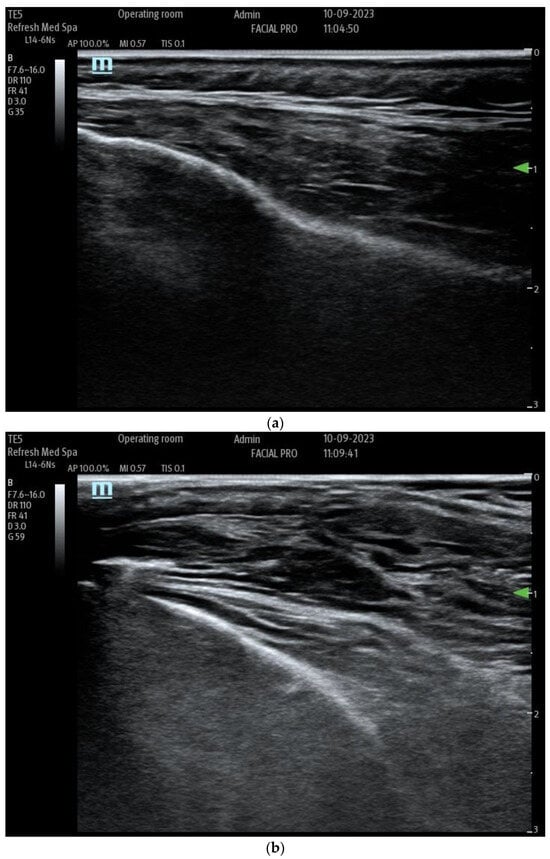

Injecting tumescent anesthesia causes the layers to space farther apart, which can be seen in real-time with ultrasound (Figure 5a,b).

Figure 5. (a) Multiple layers of superficial fascia on top of the temporalis muscle. (b) Superficial Fascia of the temple after injection of dilute local anesthetic, which widens the separation between the layers of fascia.